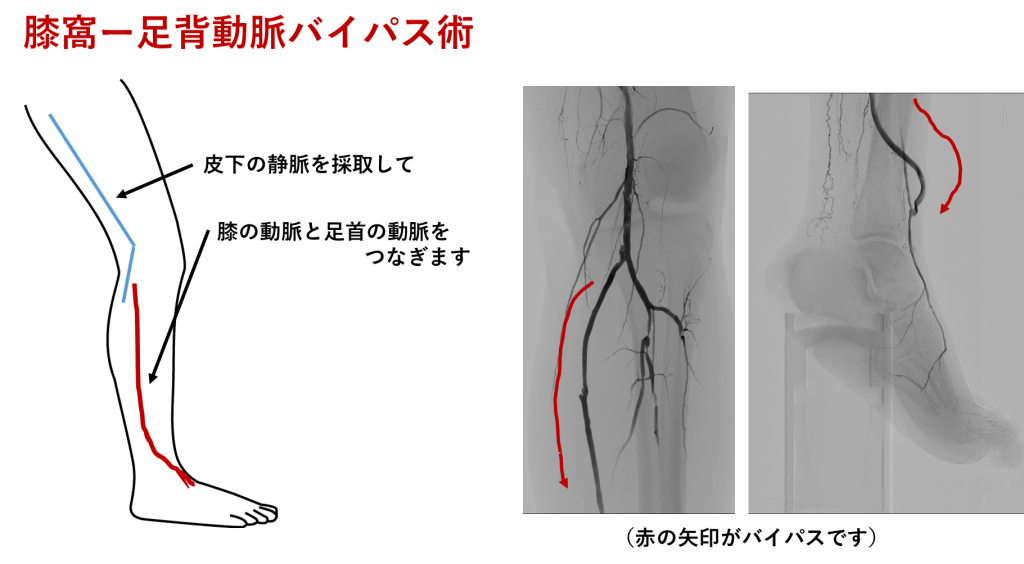

[足首の細い動脈へのバイパス(Distal bypass)]

足首や足先近くの細い血管に、太い動脈からご自身の静脈を採取してつなぎ、新しい血液の通り道を作る手術です。豊富な血流を供給できるのが特徴で、治りにくい潰瘍や壊死を伴う重症例で力を発揮します。